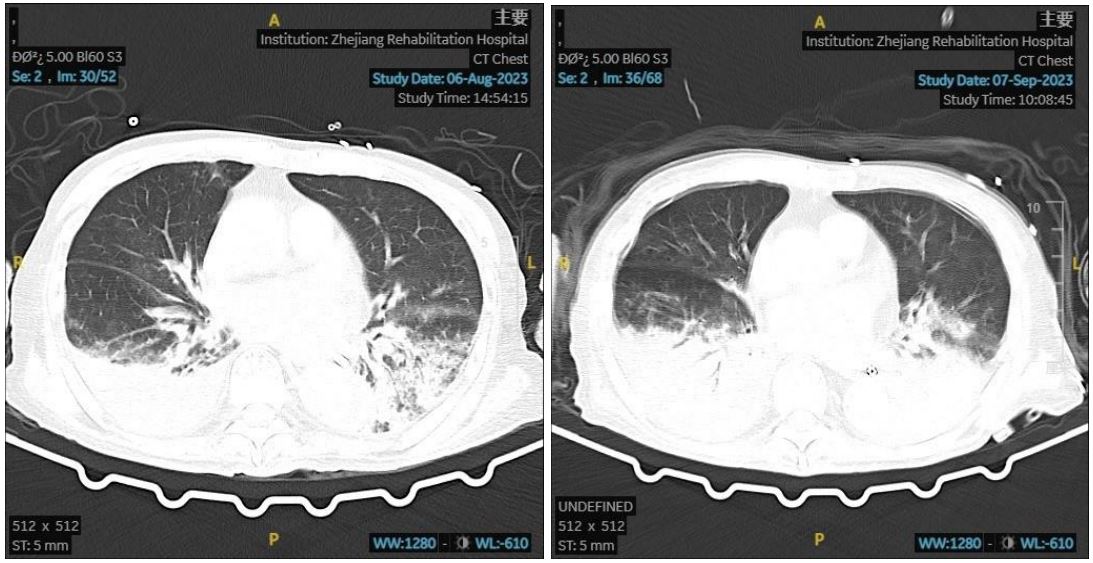

Figure 2: His CT results before and after.